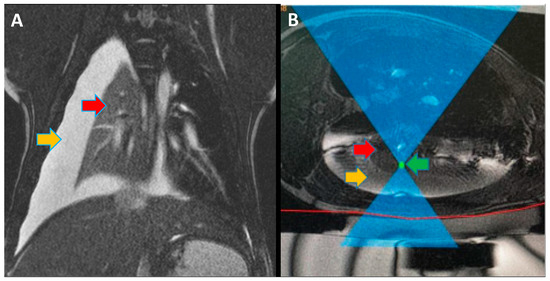

Before the procedure, Insightec Exablate software was used for the 3-dimensional planning of the treatment (Figure 1). For pigs #1–4, 45 mm UF gel pads (Insightec, Tirat Carmel, Israel) were used for cutaneous cooling, while for pigs #5–11, 25 mm UF gel pads were used (Insightec, Tirat Carmel, Israel).

Following the controlled hydrothorax, animals were transported to the MRgFUS suite, and placed in a lateral position on the MRgFUS table with the collapsed lung as the dependent lung. While in the MRI scanner, a ventilator-induced breath-hold was conducted during maximum inspiration of the ventilated lung, and ablations were conducted. An example of the software and planning used for MRgFUS ablations is shown in Figure 1. The first five pigs were treated through an escalation procedure to best determine the power required for successful ablation with minimal side effects (i.e., skin burns). The ablation energies and number of focal spots are described in Table 1.

Figure 1. (A) Magnetic resonance imaging (MRI) coronal view of pig #10 during magnetic-resonance-guided focused ultrasound (MRgFUS) treatment. Red arrow shows the collapsed non-ventilated right lung. Orange arrow shows the thoracic cavity filled with saline to create an acoustic window. (B) MRI axial view of pig #8 during MRgFUS treatment planning. Red arrow shows a collapsed non-ventilated left lung. Orange arrow shows the thoracic cavity filled with saline to create an acoustic window. Green arrow shows the focused ultrasound (FUS) focal spot targeting one of the ablation areas.